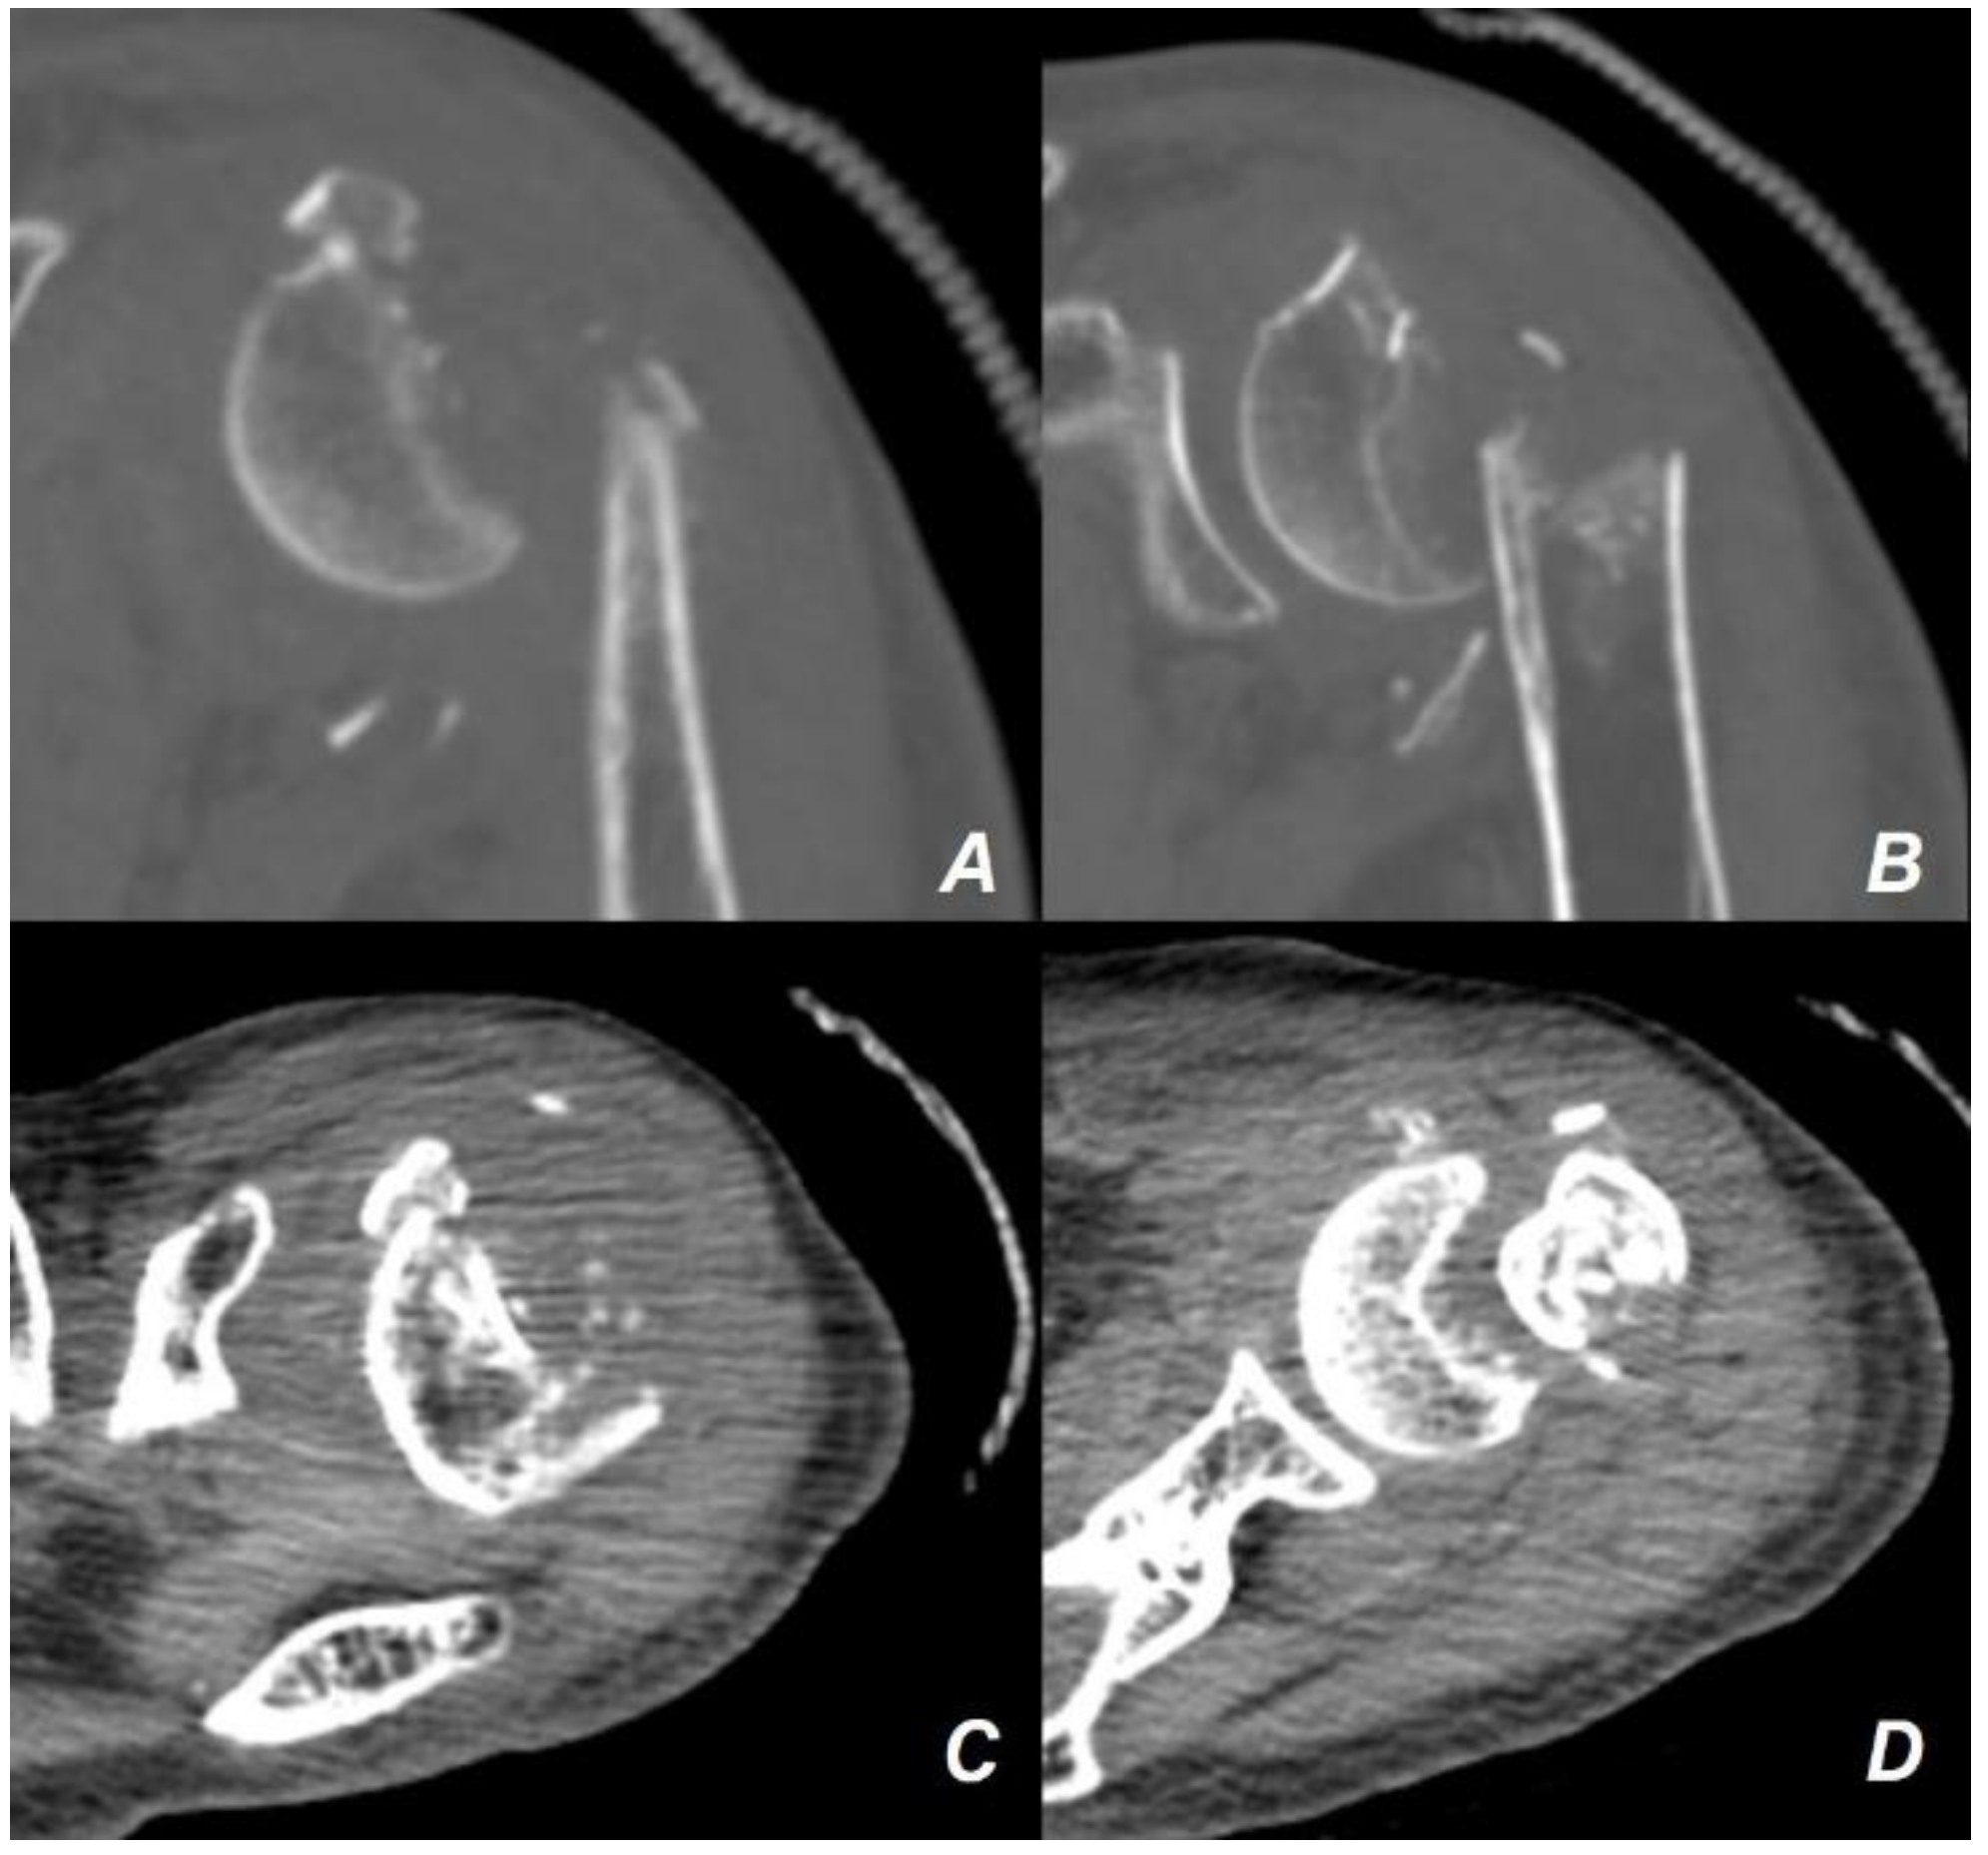

2. Case Presentation

| Age at surgery | 88 |

| Sex | Female |

| Diagnoses | Severe osteoporosis (T-score −4.6 at the femoral neck) |

| Mild hypertension on medication | |

| Neer 4-part proximal humerus fracture on the left shoulder | |

| Physical Examination | Decreased painful range of motion in the left shoulder |

| Functional demand | Independent light household activities |

| Osteoporosis medication | None |

| Past medical history | None |